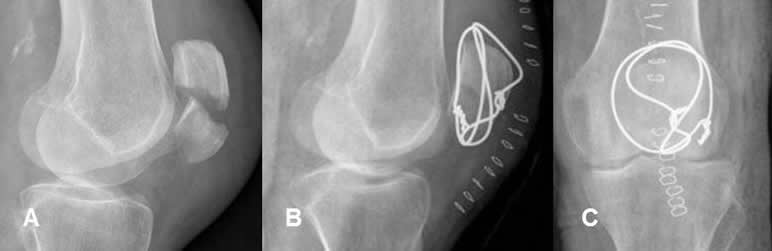

Fig 101. Cerclaje.

A: Rx lateral. Fractura transversa y con angulación anterior de la patela.

B: Rx lateral y C: Rx AP. Reducción de la fractura, mediante cerclaje con alambre.